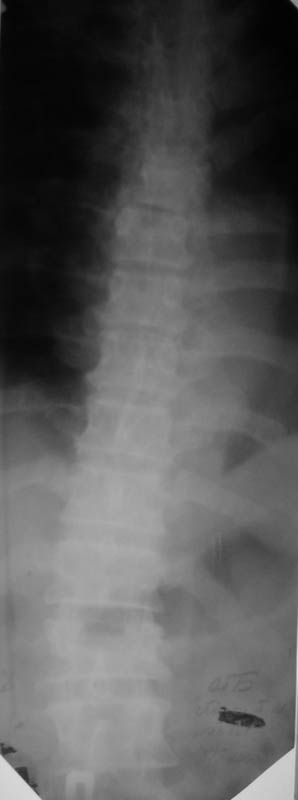

Мужчина, 48 лет. 8.04. 2000 г. - сочетанная травма: компрессионные переломы тел Th4- Тh6 и L1 позвонков с синдромом полного нарушения проводимости спинного мозга -

нижней параплегией, нарушением чувствительности и функции тазовых органов; переломы III-IV ребер справа,VI-VII ребер слева со смещением,травматический немопневмоторакс слева, гемоторакс справа, оскольчатые переломы обеих лопаток со смещением, перелом правой ключицы со смещением, тупая травма живота, ушиб сердца. Осложнения:посттравматическая пневмония, посттравматический плексит справа, цистит, пролежень в области крестца.

В настоящее время жалобы на отсутствие чувствительности в нижних конечностях, невозможность самостоятельной ходьбы (передвигается на кресле).КОНСУЛЬТАТИВНОЕ ЗАКЛЮЧЕНИЕ ЯМР-ТОМОГРАФИЧЕСКОГО ИССЛЕДОВАНИЯПроведена МР_томография грудного отдела позвоночника в сагиттальной проекции, с различной степенью контрастирования тканей, в режимах Т1 и Т2 В/И + МР-миелоурография. Визуализированы: спинной мозг с уровня D1 до уровня D12, тела позвонков D1-D12, межпозвонковые диски. Спинной мозг на уровне D4-D6 истончен с неровными нечеткими контурами, гетерогенной структуры, умеренно пониженной интенсивности на Т1 В/И, без очаговых изменений. Отмечается клиновидная деформация тела D5, снижена высота тела D4, структура его гетерогенная. Обращают внимание выраженные дегенеративные изменения дисков в грудном отделе позвоночника: снижение их высоты, изменение структуры изображения за счет исчезновения высокоинтенсивного сигнала от ядер. При исследовании в режиме МР-миелоурографии ликворный сигнал на уровне D4-D5 почти прерывается, интенсивность его существенно снижена.

ЗАКЛЮЧЕНИЕ: ПОСЛЕДСТВИЯ КОМПРЕССИОННОГО ПЕРЕЛОМА ТЕЛА D4-D5 С КОМПРЕССИЕЙ СПИННОГО МОЗГА. МРТ-ПРИЗНАКИ МИЕЛОПАТИИ И РУБЦОВО-СПАЕЧНОГО ПРОЦЕССА В ПОЗВОНОЧНОМ КАНАЛЕ НА УРОВНЕ D4-D5. ВЫРАЖЕННЫЕ ДЕГЕРАТИВНЫЕ ИЗМЕНЕНИЯ ДИСКОВ В ГРУДНОМ ОТДЕЛЕ ПОЗВОНОЧНИКА.

Уважаемый коллега, для решения о тактике дальнейшего ведения , необходимо иметь более детальную неврологическую картину - с какого сегмента идут расстройства чувствительности( какие виды чувствительности выпали), т.к если я не ошибаюсь у больного есть еще перелом L1 - на снимках его не видно.